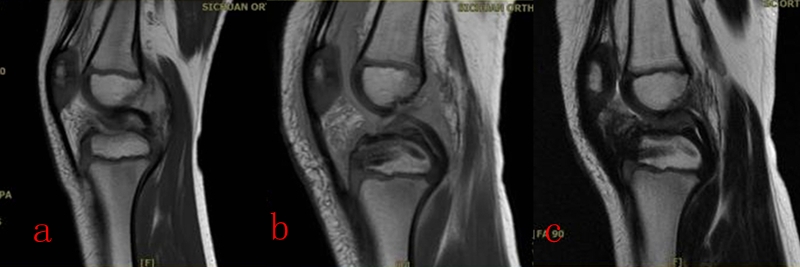

从2016年4月~2020年12月,共计25名4~11岁患儿接受了镜下手术,平均年龄9.2岁。在全部患儿中,有10名病程超过两周,属陈旧性骨折。作者采用了肩袖的镜下缝合桥技术,通过术中透视,所有的操作均在生长板上完成:在骨床后壁胫骨内、外侧髁间嵴连线中点植入一枚内排锚钉,用成角90°半月板全内缝合器将0号PDS线环在前叉韧带后内、后外两侧穿过撕脱骨块,将锚钉自带两种颜色的双骨科高强缝线分别从前叉韧带两侧过线穿过线环,并牵拉穿过撕脱骨块到达骨折表面。再将双色缝线混合引入胫骨骨床提前钻好的两个骨隧道中,双向交叉压迫于撕脱骨块上,调整骨位及缝线位置并拉紧缝线后,完成镜下复位。拉出胫骨隧道后的缝线使用一枚外排钉固定于生长板上。术毕,镜下缝线桥复位及内固定如图1所示,术前及术后MRI如图2和图3所示。术后2~3天,在疼痛缓解的前提下,开始主动康复训练。

图2 a:术前MRI;b:术后MRI